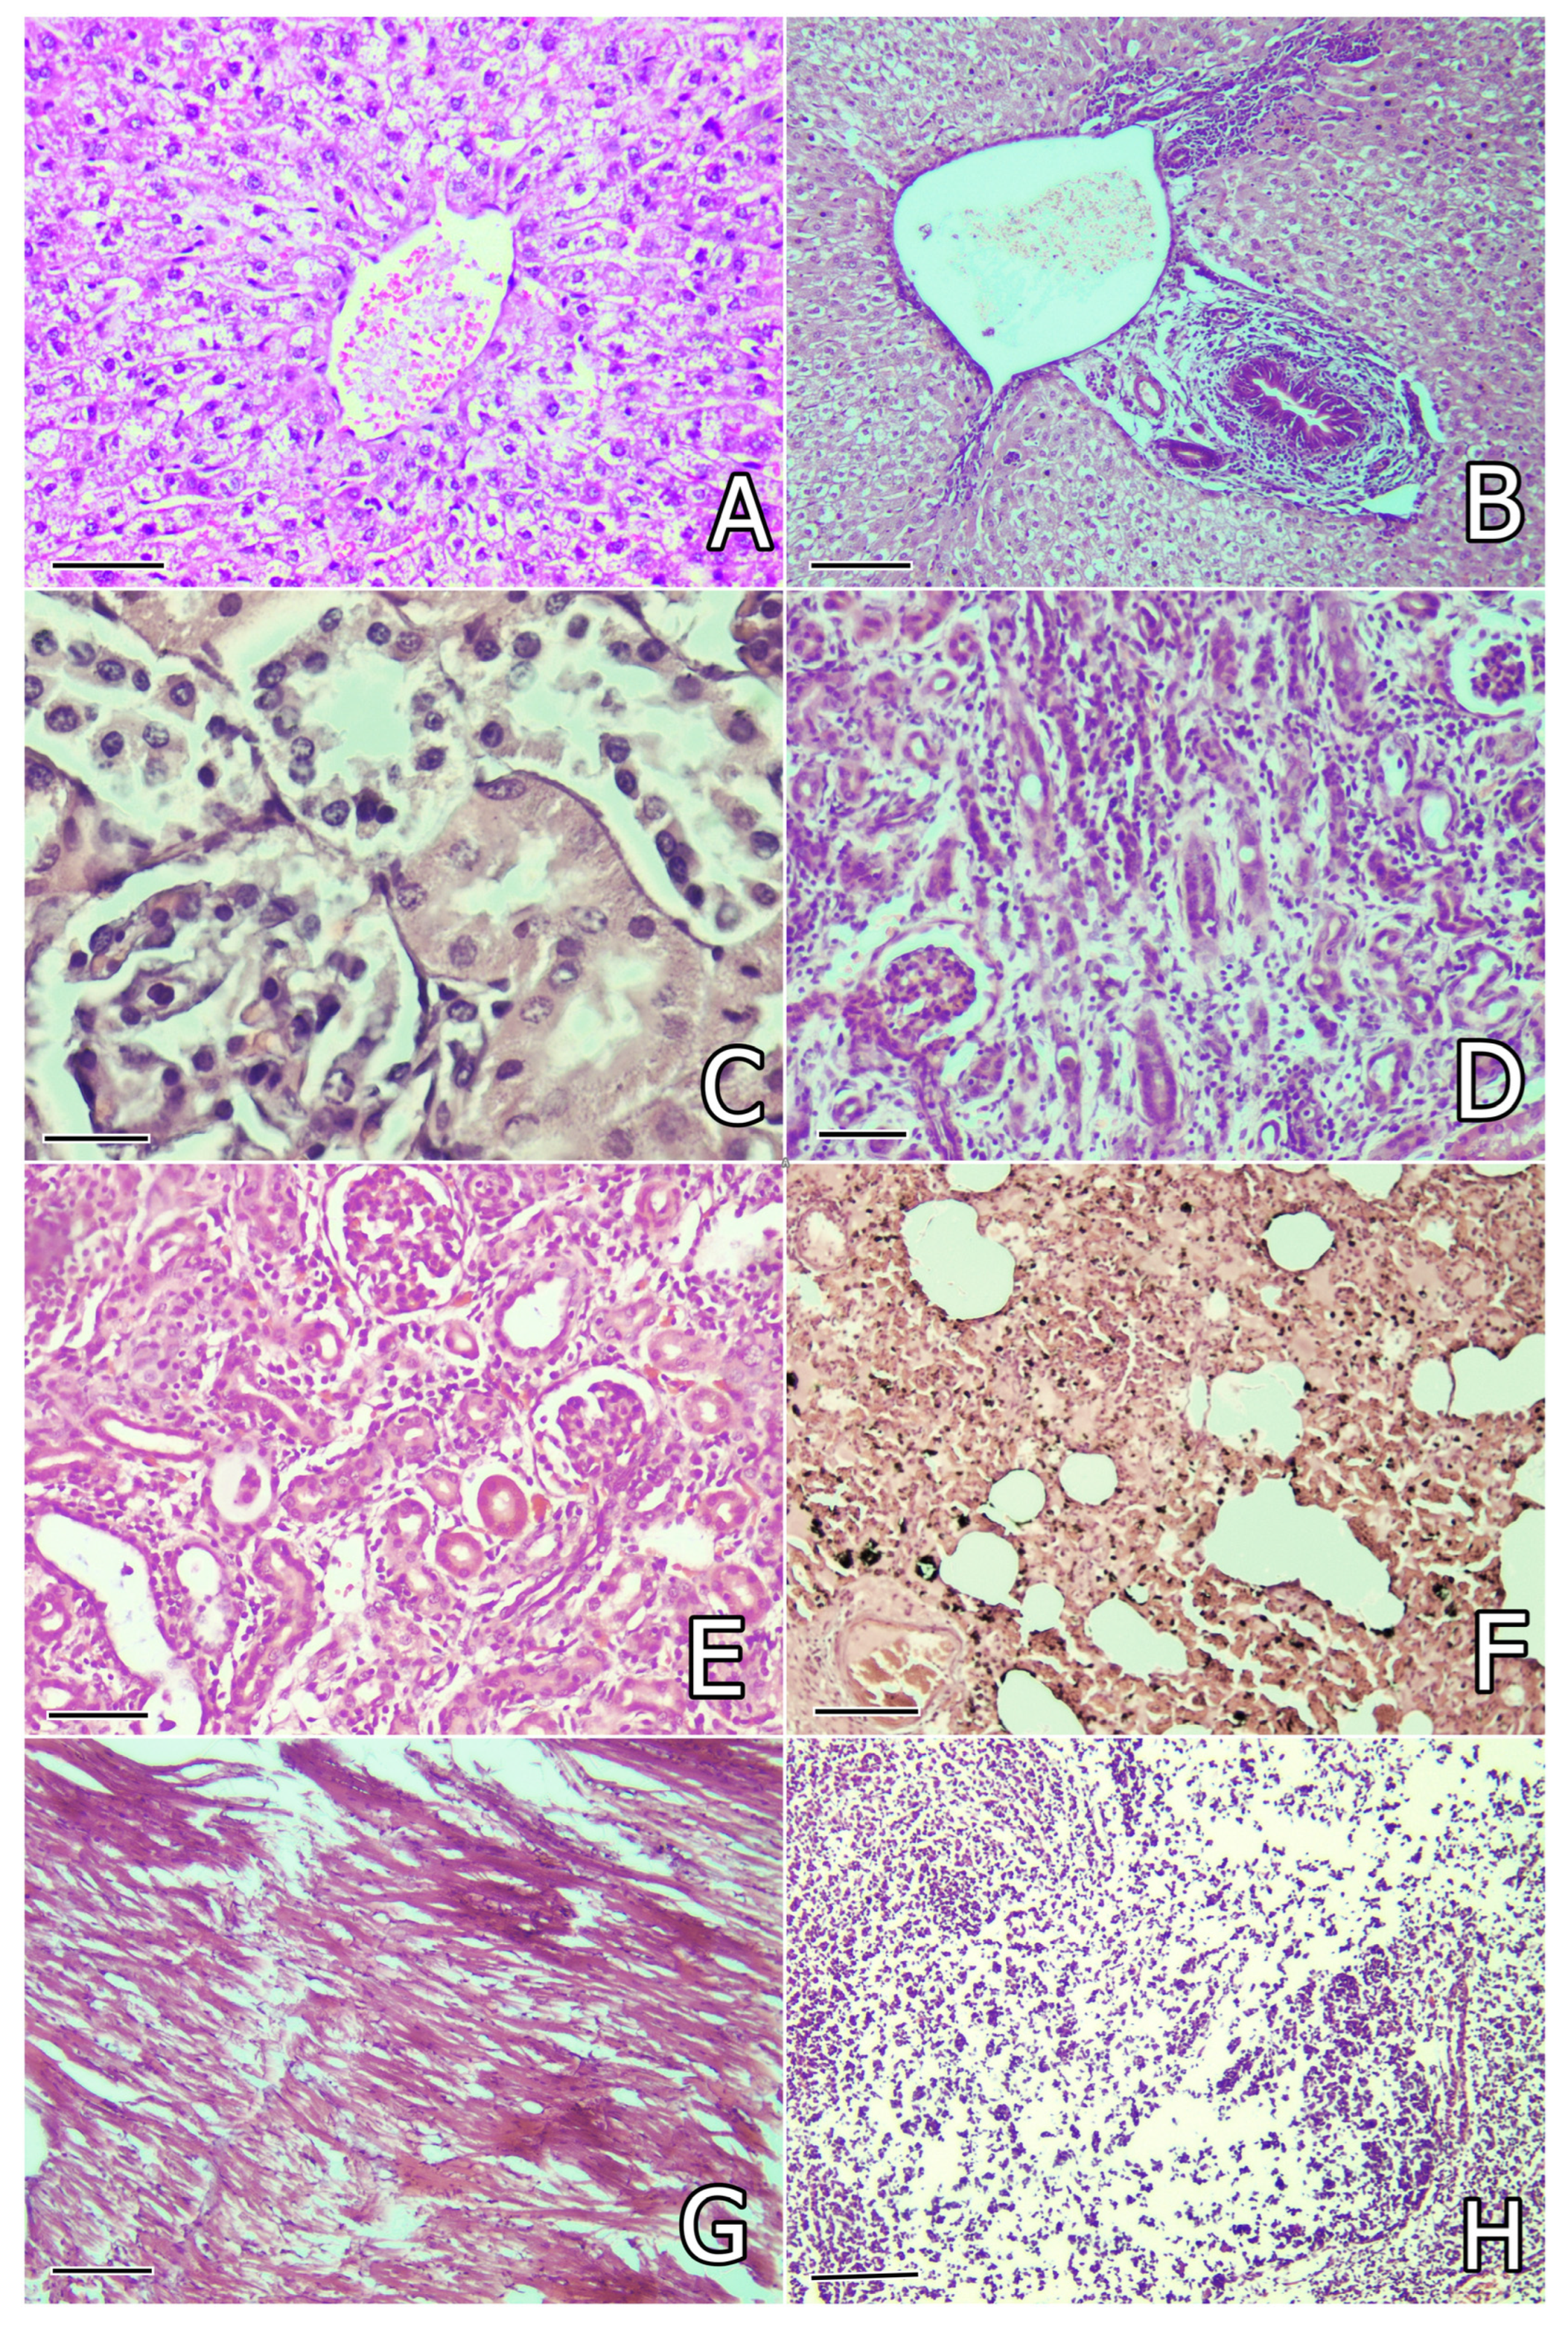

2.5. Pathomorphological Changes

2.5.1. Pathomorphological Changes on the 30th and 80th Day of the Study

2.5.2. Pathomorphological Changes in Rabbits That Died of Pasteurellosis

| Pathomorphological Changes | OTA + SIL | OTA + SM | OTA + WS | OTA + CA | OTA |

|---|---|---|---|---|---|

| Liver | |||||

| Degenerative lesions in hepatocytes | ++ | ++ | ++ | ++ | ++++ |

| Congestion or perivascular mononuclear infiltration | + | + | + | + | +++ |

| Activation of endothelial cells and Kupffer’s cells | + | + | + | + | ++ |

| Bile duct proliferation and fibrosis or edema around bile ducts | ++ | ++ | + | + | +++ |

| Focal necroses and/or fibrin accumulation in rabbits with pasteurellosis # | - | ++ | - | ++ | +++++ |

| Kidneys | |||||

| Granular degeneration in proximal tubules | ++ | ++ | ++ | ++ | ++++ |

| Congestion of peritubular capillaries | + | + | + | + | ++ |

| Inflammatory cells infiltration in interstitium | + | + | + | + | +++ |

| Endothelial proliferation in peritubular capillary | + | + | + | + | ++ |

| Proliferation of connective tissue on the 80th day * | + | - | + | - | +++ |

| Sclerosis of some glomerules on the 80th day * | - | + | + | + | +++ |

| Tubular atrophy and retention cysts on the 80th day * | - | - | + | - | +++ |

| Thrombosis of some vessels (fibrin clots) in rabbits with pasteurellosis # | - | + | - | + | ++ |

| Lung | |||||

| Congestion of vessels and presence of siderocytes | + | + | + | + | ++ |

| Peribronchial or perivascular mononuclear infiltration | + | + | + | + | ++ |

| Focal catarrhal pneumonia | + | + | + | + | ++ |

| Purulent or croupous pneumonia and/or abscesses in rabbits with pasteurellosis # | - | +++++ | - | +++++ | +++++ |

| Fibrinous pleurisy and pericarditis, incl. adhesions in rabbits with pasteurellosis # | - | +++ | - | +++ | +++++ |

| Thrombosis (fibrin clots) in vessels in rabbits with pasteurellosis # | - | +++ | - | +++ | +++++ |

| Myocardium | |||||

| Vascular congestion | + | + | + | + | ++ |

| Mononuclear cells infiltration | + | + | - | + | ++ |

| Slight granular degeneration and/or lytic changes | + | + | + | + | ++ |

| Strong granular degeneration and/or thrombosis (fibrin clots) in vessels in rabbits with pasteurellosis # | - | ++ | - | ++ | +++++ |

| Spleen | |||||

| Degenerative lesions in white pulp | - | + | - | + | ++ |

| Depletion of cells in white pulp | - | + | + | ++ | +++ |

| White pulp reduction and predomination of red pulp in rabbits with pasteurellosis # | - | ++ | - | ++ | +++ |

| Thymus | |||||

| Degenerative lesions or depletion of cells in cortex | + | + | + | ++ | +++ |

| Intestines | |||||

| Degenerative lesions of surface/glandular epithelium | + | + | + | + | ++ |

| Brain | |||||

| Lytic/pyknotic changes in tigroid substance of neurons | + | + | + | + | ++ |

| Lytic changes in brain substance | + | + | + | + | ++ |

| Pericapillary and pericellular edema | + | + | + | + | ++ |

| Pericapillary infiltration with lymphocytes | - | - | - | - | ++ |

| Focal proliferation of microglia | - | - | - | - | ++ |

| Cerebellum | |||||

| Lytic changes in lamina medullaris or Purkinje cells | + | + | + | + | ++ |

| Ovary | |||||

| Connective tissue proliferation and interstitial edema on the 80th day * | + | + | + | + | ++ |

| Vascular congestion | - | - | - | - | + |

| Testicles | |||||

| Degenerative lesions in seminiferous tubules on the 80th day * | + | + | + | + | ++ |

| Interstitial edema on the 80th day * | + | + | + | + | ++ |